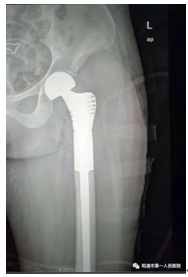

三小时余,180多分钟,10800多秒。这个时间段内,因肿瘤累及股骨近端,须先进行肿瘤切除,随后进行关节置换,把定制的特殊关节假体植入,再进行缝合。这个时间你也许看完一场《复联4》电影,也许坐在街角的咖啡厅小憩看完几章书节,或是刷着抖音愉快了个下午,然而在手术台上的团队却没那么轻松,手术护士目不转睛盯着仪器闪烁着的数据,一边报告患者生命指征情况,一边马不停蹄递上器械,麻师寸步不离为团队提供必要的协助,主刀医生反复根据术中情况清醒而迅速的应对,这样的全神贯注和身心绷紧的场合可不是一般人所能体会和想象。

(术后影像图)

当剪刀轻轻夹断缝合线节发出轻微脆响后,一双双年轻而内敛的眼睛似乎带着笑意。患者生命指征一切正常,仪器一连串的滴答声无不在祝贺在场的医护。这是没有硝烟的战场,最后也没有鲜花和掌声,大家摘下口罩长舒的一口气,这是空气凝结后瞬间的释放,是一颗颗赤子之心汹涌而澎湃的颤动。